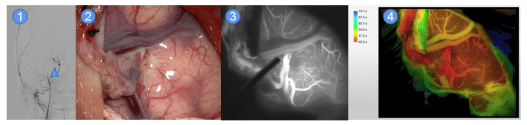

烟雾病的脑血管低流量搭桥手术:脑血管搭桥是治疗烟雾病的重要手段

1)颅内血运严重不足,2)术中搭桥完成,3)荧光造影显示通畅(白色),4)术中造影显示脑供血明显灌注改善(红色区域)